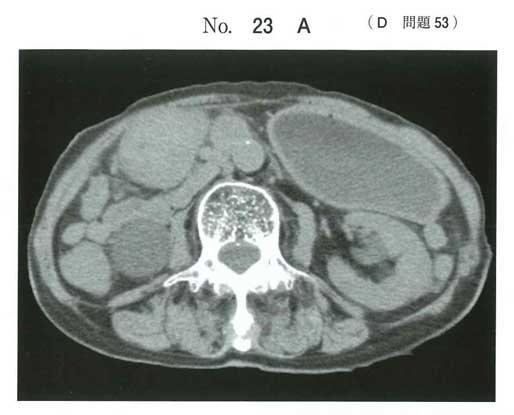

経過と腫瘍マーカー、CTで胃幽門部の壁肥厚から胃癌疑い。それで通過障害があるんですかね。

模試で出まくっていたSMA症候群な気もしますね。

CEA高値は悪性腫瘍による体重減少→二次的にSMA症候群発症の流れかなと思います。